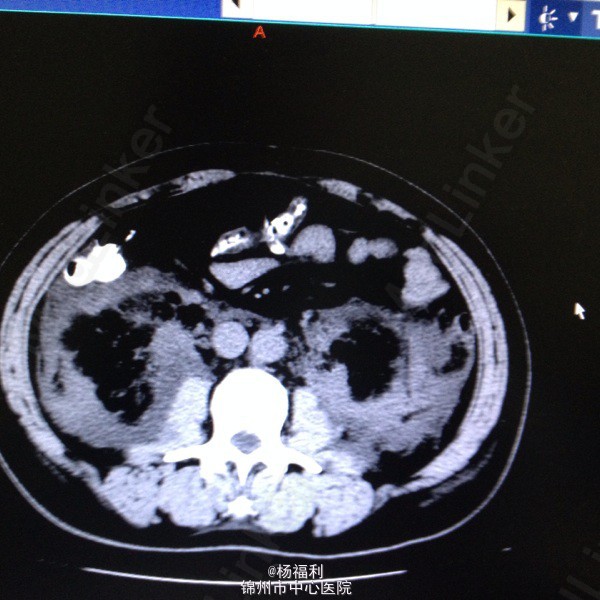

44岁女患。为消化科我会诊患者。 现病史:以上腹痛9小时为主诉入院。无发热及寒战、噁心未呕吐,无腹泻及黑便。 既往史:双眶炎性假瘤2年,口服激素治疗,并补钾。

查体:上腹部压痛,无反跳痛、右侧压痛明显,右肾区叩击痛,左肾区轻叩击痛,双输尿管走形区无压痛。 辅助检查;泌尿系彩超:双肾积水。 血白细胞:9.99*10^9。 肾功能正常。 全腹部ct及MRU检查:见图片。

诊断;真的不知道是啥病。 处理:暂时止痛处理。双肾病变。不知从哪里下手。